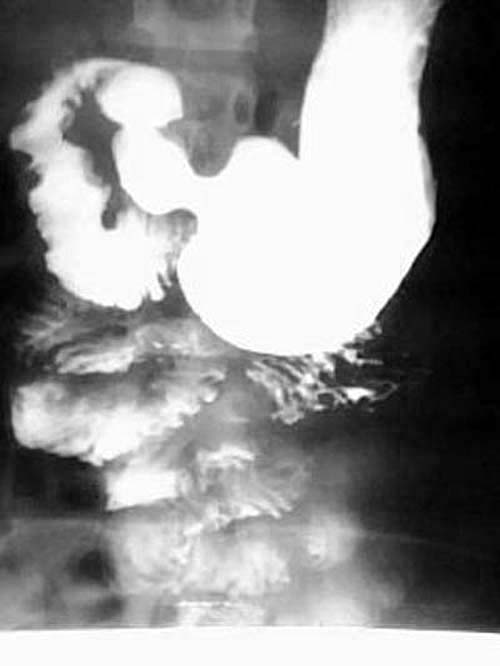

女性,12岁,因腹痛,恶心呕吐一周,腹呈绞痛,痛时可扪及包块,呕吐物为胆汁.大便不成形.于外院输液无好转(具体不详),遂转入我院,经对症治疗3天后好转,

卧位摄片:

ped0661结果:中肠旋转不良伴中肠扭转.为手术所证实

本例是典型的中肠旋转不良伴中肠扭转的病例.为手术所证实.

本例临床表现是上消化道梗阻的表现.但初入院时外科诊断并不明确.透视未见明显异常(其他医生作的,具体不详),两次超声均未能明确诊断.入院后行禁食,胃肠减压,对症,输液等处理,约3天后腹痛缓解.拔胃管的当天吃了二个小包子,第二天作钡餐,钡餐示:十二指肠水平段不全梗阻(腹膜带压迫),空肠在左上腹小段盘曲后随即转向右,并于中腹部呈螺旋形下降(这是中肠旋转不良伴中肠扭转的典型表现),大部份回肠位于左下腹.因外科开的是上消化道钡餐,我已经把大部份小肠都看了,又到了下班时间,就没有继续往下追踪,如果断续追踪发现盲肠的位置异常,则可进一步的证实和肯定诊断.

中肠的旋转不良合并扭转在术前是可以确诊的,肠旋转不良作钡餐时不时可以见到,但合并扭转的并不多。根据本人体会及结合文献,中肠的旋转不良合并扭转,可以没有肠梗阻,但也可以有梗阻,甚至绞窄,坏死。几年前我也遇见过一位成人的小肠旋转不良伴扭转的病例.患者大约四、五十岁.没有明显肠梗阻,(遗憾的是胶片已销毁,不然可请老师们鉴别一下)。但不论有无梗阻,一旦发现有扭转均为手术指征。

钡餐检查可获得肠旋转不良的全部信息,包括十二指肠有无梗阻、十二指肠空肠曲位置、有无肠扭转及回盲部位置,是诊断本病的首选方法。钡灌肠造影发现回盲部在左腹部或右上腹部,可确诊肠旋转不良,但不能诊断是否并发中肠扭转。